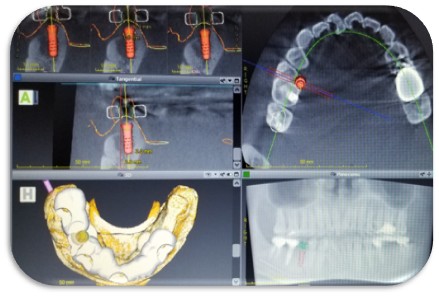

またインプラント治療も安全性に配慮した治療を心掛けており、全症例デジタルシュミレーションソフトによるガイドシステムを用いたインプラント治療が定評で、多くの患者さんの施術をおこなっております。